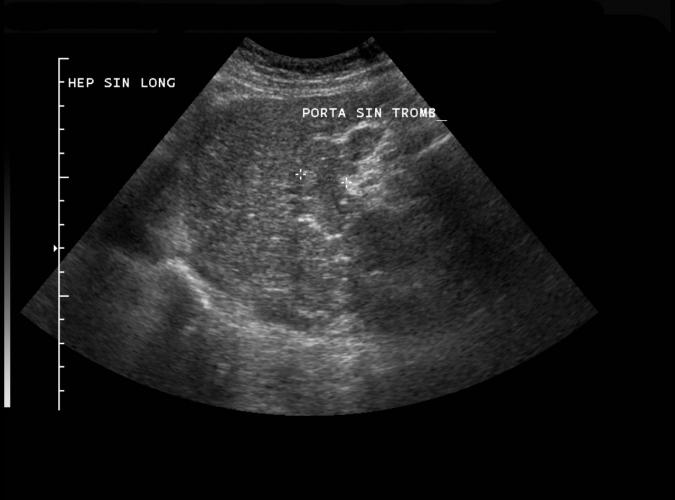

Long vänster leverlob. Trombotiserad porta sinister